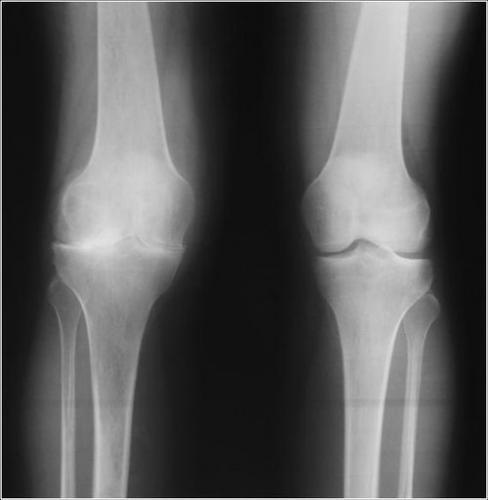

Большинство видов артрозов хорошо заметны на рентгенографическом снимке, проведенном в нескольких проекциях. Рентген показывает не только артроз, но и осложнения его длительного протекания (включая поражение мягких тканей).

На рентгене можно без труда обнаружить запущенные стадии артрозов, но на начальных стадиях могут возникать проблемы. Неопытность рентгенолога или нестандартное течение болезни (что называется «не по учебнику») может привести к пропуску заболевания на ранней стадии. Чтобы этого не произошло, при наличии подозрений рекомендуется посетить консультации у нескольких врачей.

Увидеть на рентгенографии признаки артроза на 2-4 стадии обычно не представляется сложным (особенно при поражении стоп и колена), если только не брать в расчет редкие формы заболевания.

Сложнее с первой степенью болезни – в начале развития ее нередко пропускают, особенно если диагностика проводилась не в профильном стационаре.

Современная медицина выделяет три рентген-стадии остеоартроза. Они отличаются следующими симптомами и формой протекания патологии:

- При первой стадии у пациента начинается сужение просвета суставной щели, а также минимальное разрастание хрящевой ткани. Видимых признаков заболевания пока нет, но при интенсивных нагрузках симптоматика становится более выраженной.

- Переход остеоартроза на вторую стадию вызывает несколько структурных изменений. В первую очередь происходит разрастание костной ткани и формирование остеофитов. При рентгеновском обследовании отображается существенное сужение суставной щели, а во время визуального осмотра замечается сильная деформация суставных поверхностей.

- Третья стадия заболевания считается самой тяжелой и практически не поддается консервативному лечению. В этот период суставная щель практически не просматривается, т. к. она полностью заполняется наростами костной ткани. Внешние очертания суставов становятся уродливыми, а на снимке заметны склеротические изменения.

Основной чертой развития артроза являются значительные болевые синдромы, при этом на рентген-снимке морфологические метаморфозы могут быть практически незаметны. Случается и обратная клиническая картина, у пациента практически не наблюдаются неприятные ощущения, но при этом на снимке видны многочисленные изменения.

- На начальной стадии наблюдается еле заметное сужение суставной щели. При этой форме заболевания поражаются только лишь хрящи суставов.

- На следующей, второй, стадии уже значительно выражены патологические изменения. Сужение щели суставов отлично визуализируется и имеет неравномерные контуры. Хрящи начинают разрушаться в месте наибольшей нагрузки. На снимках диагностируется субхондральный остеосклероз.

- На третьей стадии видны четко выраженные необратимые изменения. Хрящи становятся рыхлыми и практически полностью разрушаются. Наблюдается явная дисфункция больного сустава. Эта стадия показана на фото.

Рентген суставов при артрозе поможет раньше диагностировать заболевание, вследствие чего проще будет купировать болезненные симптомы.Степени артроза на рентгене отлично визуализируются, и опытным врачом-рентгенологом легкорасшифровываются и описываются.